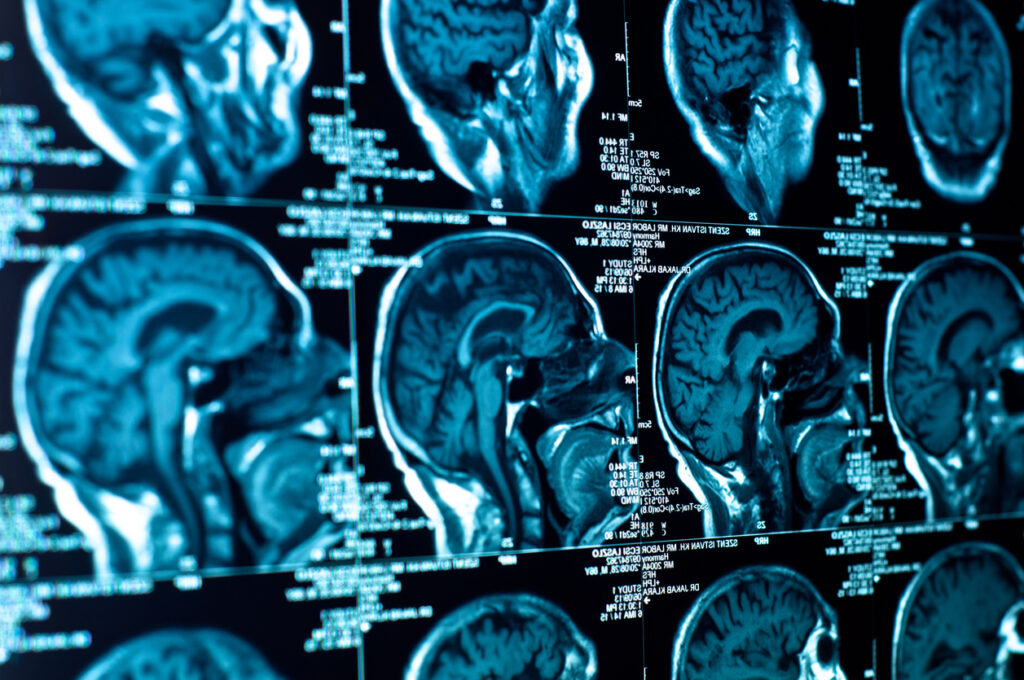

Traditionally, patients undergo regular scans to assess the effectiveness of chemotherapy. However, this approach carries the risk of subjecting individuals to ineffective treatments and harmful side effects. The AI model, trained on a vast dataset comprising tens of thousands of scans from diverse brain cancer patients, revolutionizes this process. By offering an instantaneous and accurate prediction based on routine MRI scans, clinicians can now identify patients who may not benefit from chemotherapy. This allows for a more personalized and precise approach, steering patients toward alternative treatments or participation in experimental clinical trials.